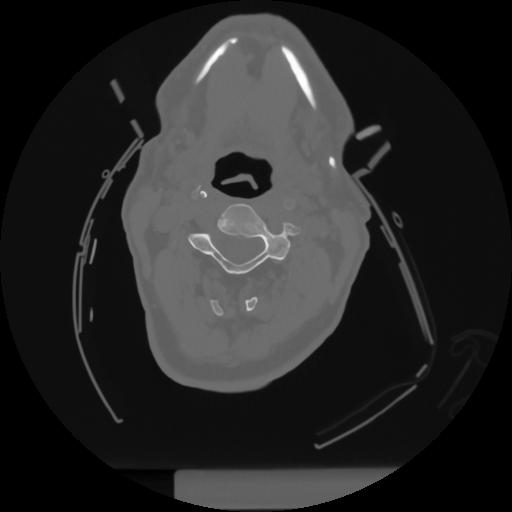

12 P.BLANDAS,,Vol,0.5,P.BLANDAS,,